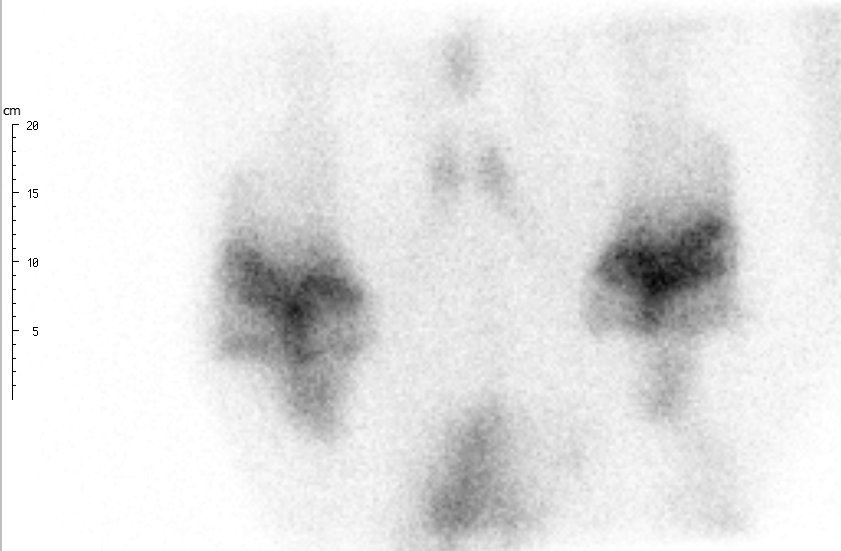

Real-Time Motion Correction: Faster Scans, Enhanced Quality

ParalyzerPLUS

ParalyzerPLUS raw study

raw study ParalyzerPLUS

ParalyzerPLUS raw study

raw study ParalyzerPLUS

ParalyzerPLUS raw study

raw study ParalyzerPLUS

ParalyzerPLUS raw study

raw studySelection of possible studies